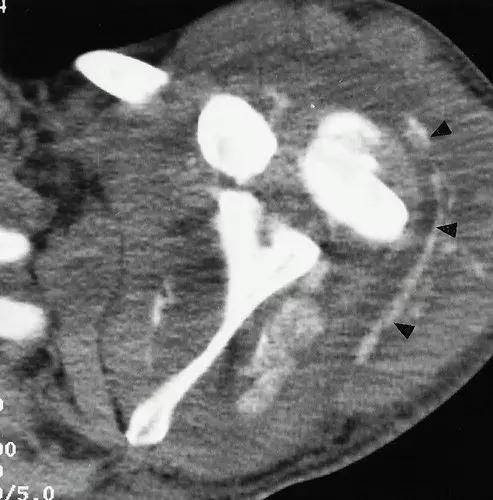

图3:患者28岁,T8截瘫,肩部神经性骨关节病。 (a)胸部X线片显示左盂肱关节实质性破坏(实线箭头)。 注意脊柱固定硬件(空心箭头)。 (b)轴向CT扫描显示由低衰减液体扩张的关节内衬的骨质碎片(箭头)。 (c)颈椎的T2加权自旋回波MR图像(2,400 / 80)显示广泛的空洞。